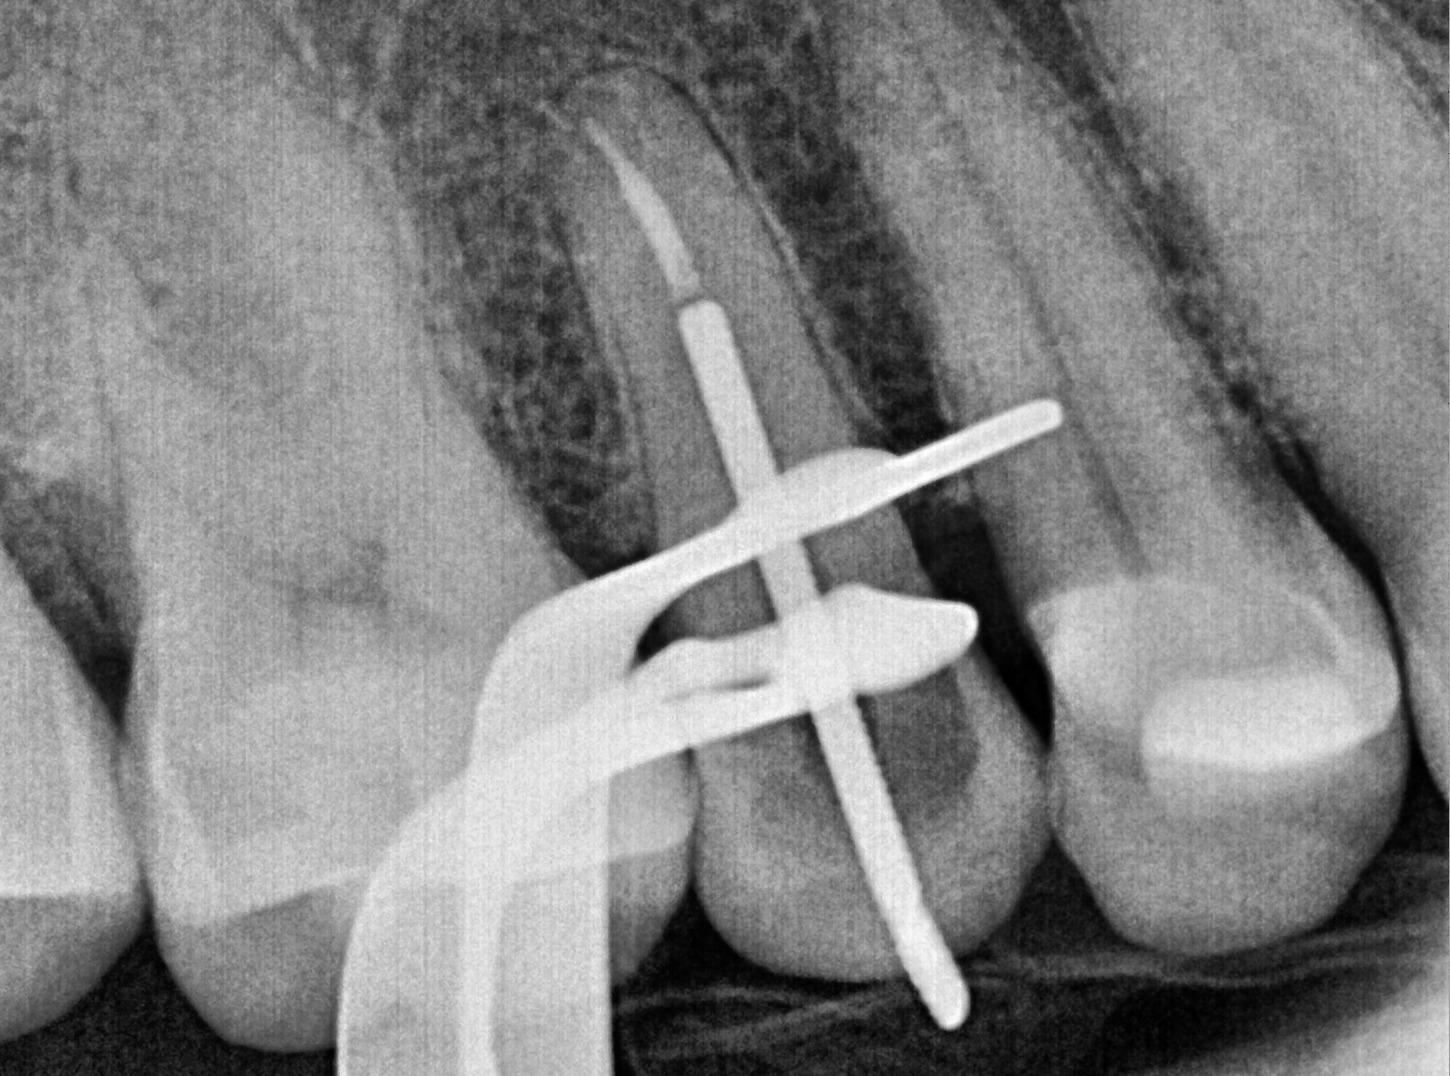

Obturation & Post Placement #4

● Placed a post and core as requested by the referring dentist

Post placement

The patient handled the procedure very well, and everything went smoothly. We shared pre-op and post-op radiographs with the referring dentist for their records.Patient headed straight to the dentists office for a crown.

Final PA#4 after post & core